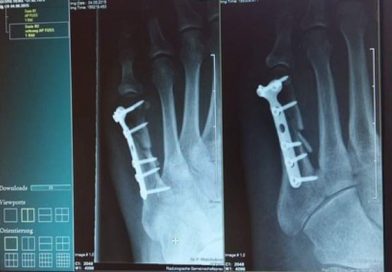

Saiba Tudo Sobre Fraturas E Como Fazer Os Primeiros Socorros O Que É Uma Fratura (Osso Quebrado)? Uma fratura acontece